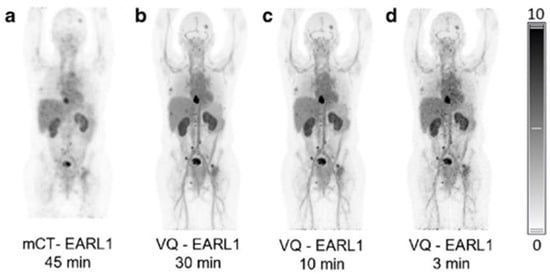

- Hu, P.; Zhang, Y.; Yu, H.; Chen, S.; Tan, H.; Qi, C.; Dong, Y.; Wang, Y.; Deng, Z.; Shi, H. Total-body (18)F-FDG PET/CT scan in oncology patients: How fast could it be? Eur. J. Nucl. Med. Mol. Imaging 2021, 48, 2384–2394. [Google Scholar] [CrossRef]

- Alberts, I.; Hunermund, J.N.; Prenosil, G.; Mingels, C.; Bohn, K.P.; Viscione, M.; Sari, H.; Vollnberg, B.; Shi, K.; Afshar-Oromieh, A.; et al. Clinical performance of long axial field of view PET/CT: A head-to-head intra-individual comparison of the Biograph Vision Quadra with the Biograph Vision PET/CT. Eur. J. Nucl. Med. Mol. Imaging 2021, 48, 2395–2404. [Google Scholar] [CrossRef]